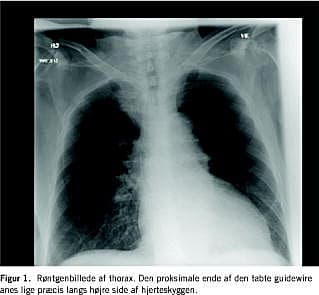

En 74-årig kvinde gennemgik et længere ortopædkirurgisk behandlingsforløb og fik i den forbindelse anlagt CVK tre gange. De to første anlæggelser var komplikationsfri. Ved den tredje CVK-anlæggelse forsøgte man ved Seldingers teknik (som tidligere) ultralydvejledt at anlægge kateter i v. jugularis int. dxt., men guidewiren kunne ikke indføres. Patienten havde desværre svært ved at kooperere ved indgrebet, hvorfor der hurtigt blev anlagt et CVK (1-lumen, 15 cm langt) i v. jugularis ext. sin. af en mere erfaren anæstesiolog. Der var frit frem- og tilbageløb, og der blev taget kontrolrøngten af thorax efter en time (Figur 1 ). Den umiddelbare røntgenkontrol, som blev set via PACS på en »lokal« skærm, gav ikke mistanke om fejlplacering eller komplikationer, og røntgenbeskrivelsen fra radiologisk afdeling dagen efter angav normale forhold, bortset fra at CVK nåede helt ned i v. cava inf.

Ud over at sygehistorien illustrerer muligheden for at begå en sjælden, men forebyggelig fejl [5], belyser den et problem, der kan opstå, når røntgenbilleder overføres elektronisk til en lang række skærme, som har dårlig opløsning og ikke jævnligt kalibreres. Den læge, der via PACS kontrollerede CVK'ets placering efter anlæggelse, bemærkede ikke guidewiren. Grunden var, at den pc-skærm, der var til rådighed, ikke var korrekt kalibreret. Skærmens opløsning var ringe, hvilket gjorde det umuligt at se guidewiren, der var »skjult« af hjerteskyggen.